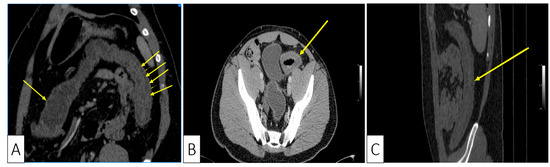

| Our patient | Male, 30 | Colicky left lower quadrant abdominal pain and bloody diarrhea | Negative fecal culture, positive toxins A, B, and GDH | Idiopathic | Several superficial longitudinal ulcerations with luminal narrowing spanning from sigmoid to the descending colon | Desquamation of superficial epithelium with focal necrosis, loss of superficial glands, edematous and necrotic lamina propria | Oral Vancomycin, symptoms resolved within two days of hospitalization |